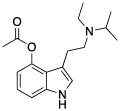

| 4-AcO-DMT | artificial | 4-OCOCH3 | CH3 | CH3 | 4-acetoxy-N,N-dimethyltryptamine | 92292-84-7 |